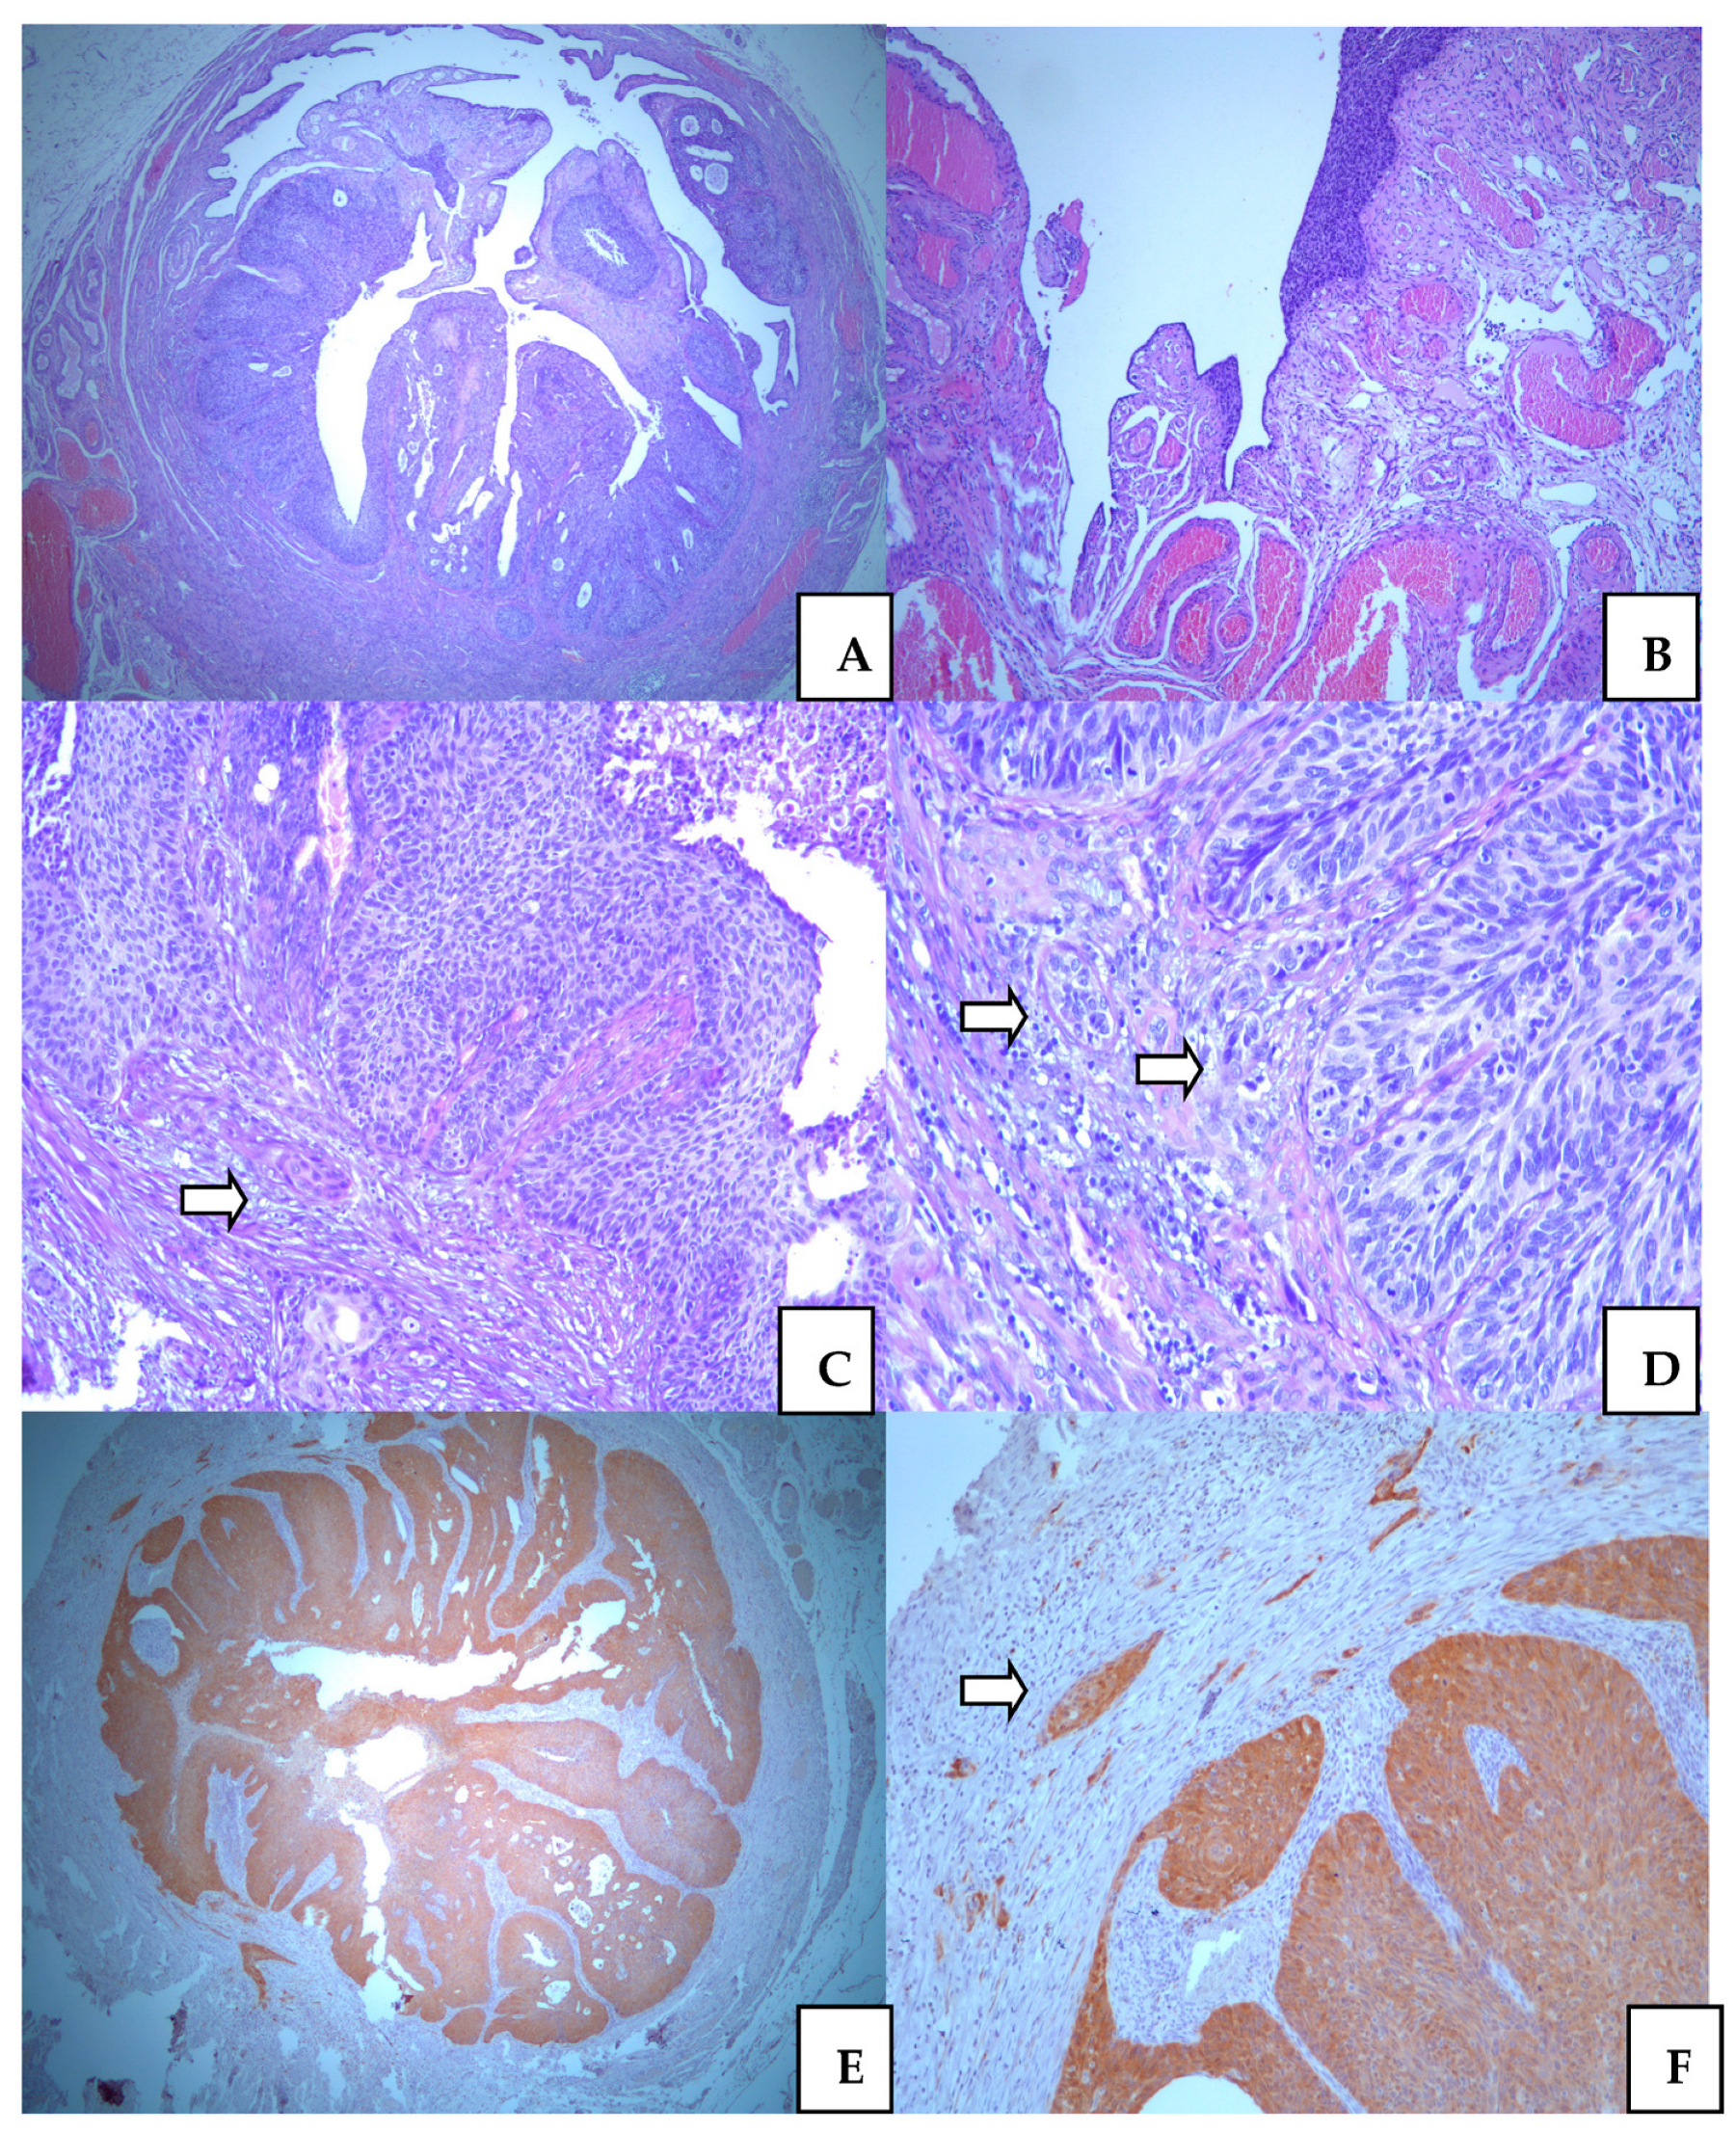

Dysplastic high-grade epithelial lesions were predominant in all specimens. Microinvasive focus was in the subisthmical parts of cervical stroma measured 1mm deep. It was a very discrete focus presented as small cell clusters with atypical cancer cells, surrounded by intensive lymphocyte inflammatory reaction. The lymphovascular invasion was not found. These features are presented in Figure 2.

Ovaries were without malignant features. There were benign, simplex cysts surrounded by slightly hyperthecosus ovarian stroma. In the right tubal epithelium, we found segments with remarkable intraepithelial cancer in in situ lesions. The altered epithelium was stratified, with marked atypia and increase mitotic figures. On the very extended series of histology sections, we noticed microinvasive SCC focuses in the tubal wall. The depth of invasion was not more than 1mm. However, unlike SCC, in the cervix, here we additionally observed invasion of lymphatic and vascular vessels. The microscopic pattern of SCC is more aggressive in tubal than in cervical tissue. Tubal involvement of SCC was presented in Figure 4. Additional extirpated lymph nodes did not show metastatic lesions.

Figure 4. Squamocellular carcinoma in the uterine tuba. Intraepithelial neoplastic lesion replaces normal tubal epithelium ((A). ×25, and (B). ×50); Microinvasive foci (arrows) in surronding fibrous tissue of tubal wall ((C). ×100, and (D) ×100); Positive p16 immunostaining in neoplastic epithel with remarkable expression in micorinvasive foci (arrow) ((E). ×25, and (F). ×100).